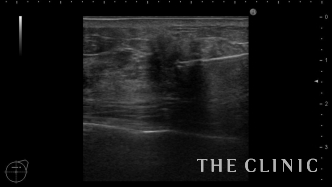

このしこりは石灰化の近くにオイルシストを認めます。

オイルシスト部分のみを穿刺吸引しましたが、ある程度はしこりを触れにくくなります。

除去したオイルです。